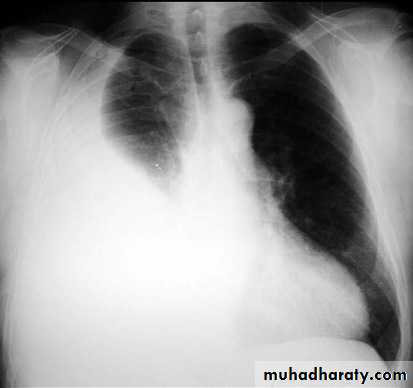

with large volume effusions, mediastinal shift occurs away from the effusion (note: if coexistent collapse dominates then mediastinal shift may occur towards the effusion)

An empyema can resemble a pleural effusion

and can mimic a peripheral pulmonary abscess, although a number of features usually enable distinction between the two Features that help distinguish a pleural effusion from an empyema include:Shape and location

Empyemas usually:

form an obtuse angle with the chest wall

unilateral or markedly asymmetric whereas pleural effusions are (if of any significant size) usually bilateral and similar in size .

lenticular in shape (bi-convex), whereas pleural effusions are crescentic in shape (i.e concave towards the lung)

Empyema